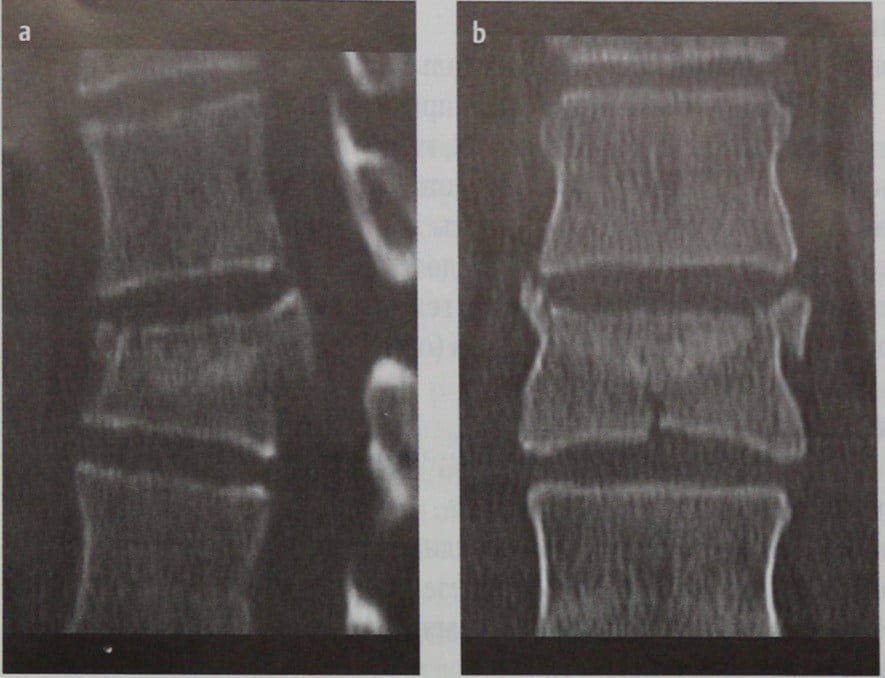

Рентгеновские снимки и медицинские изображения компрессионных переломов